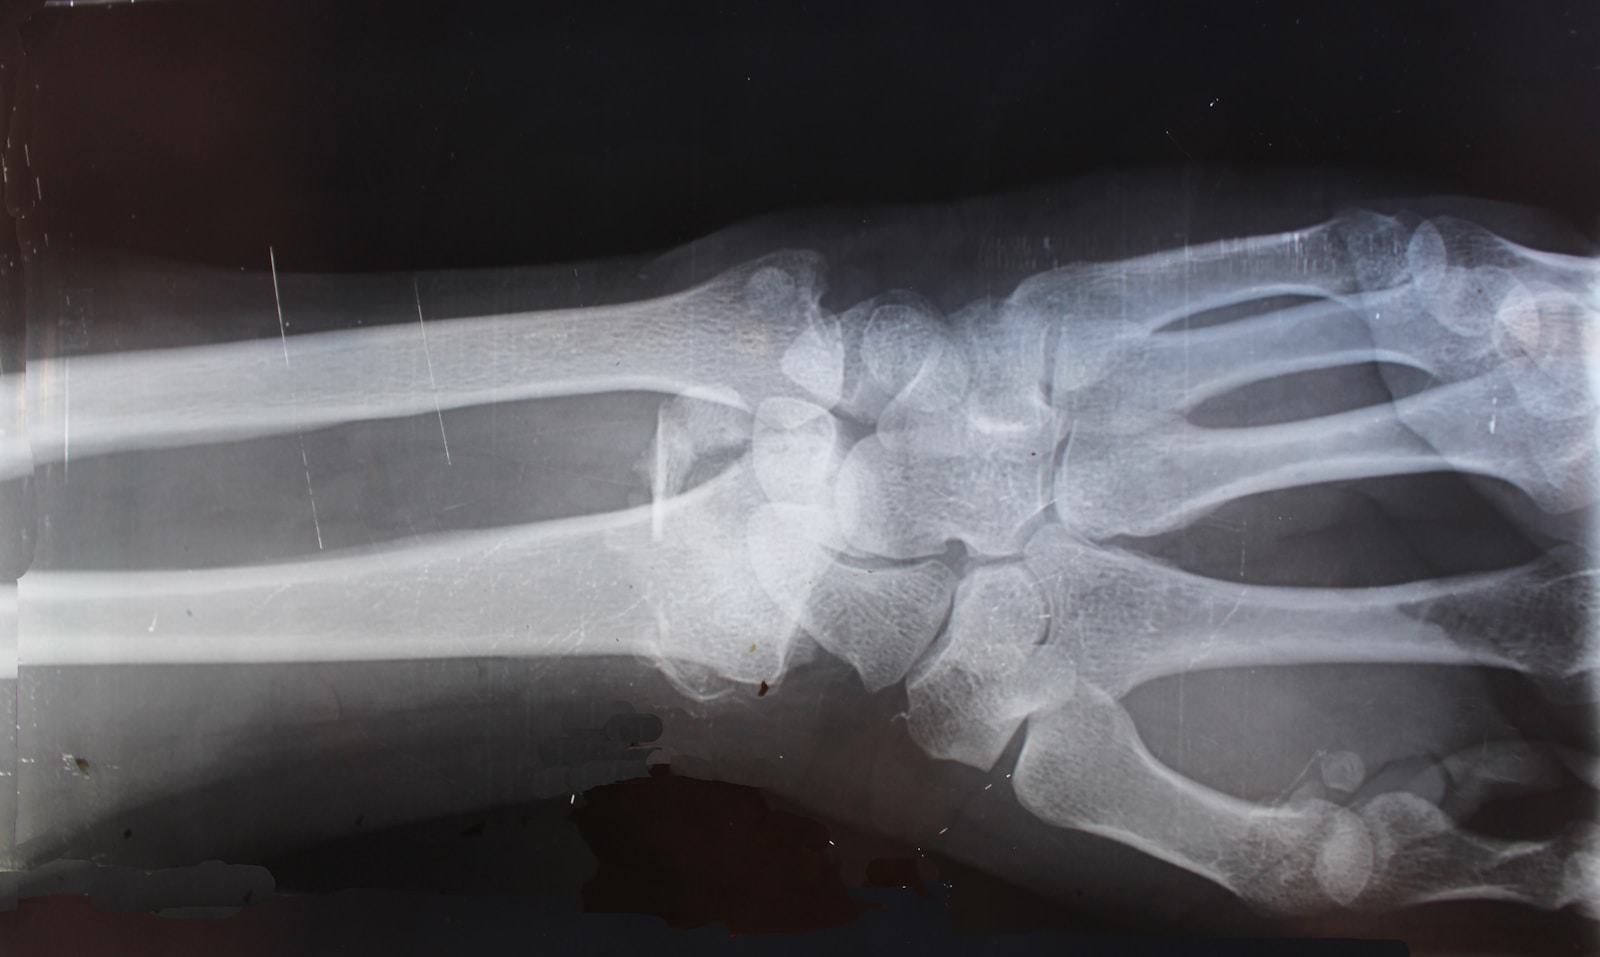

El dolor crónico y las lesiones pueden limitar su capacidad para disfrutar de la vida, pero un diagnóstico preciso es el primer paso para una recuperación exitosa. En ABC Rehab and Chiropractic, contamos con tecnología avanzada de Rayos X para identificar la causa raíz de su malestar y diseñar un plan de tratamiento efectivo para diversas condiciones, incluyendo:

- Fracturas y Fisuras Óseas

Nuestro sistema de radiología digital de última generación nos permite obtener imágenes claras y detalladas de su estructura ósea de manera rápida y segura. Esto nos ayuda a visualizar exactamente lo que está sucediendo en su cuerpo, eliminando las conjeturas y permitiéndonos aplicar ajustes y terapias con la máxima precisión.